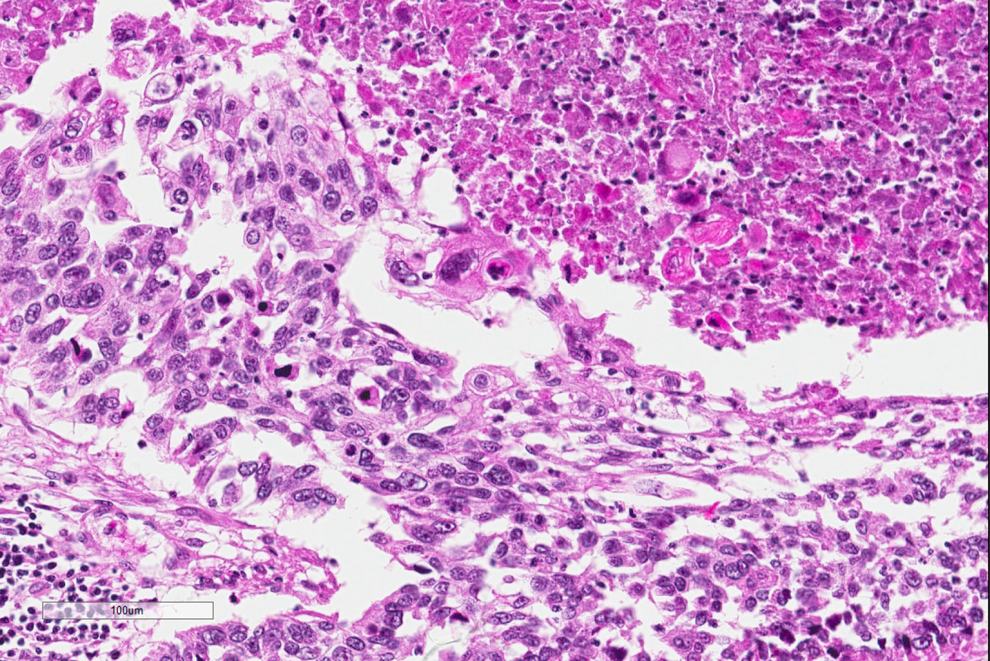

A biopsy was performed because of the high clinical suspicion of a malignant lesion. Figures 1 to 3 show representative histologic features of the biopsy on low, medium, and high power.

Histopathology of the lung biopsy. A low-power image showing extensive tumor on the right hand side, with nests of tumor cells infiltrating into the pulmonary parenchyma on the left.

Higher power image of the tumor with neoplastic cells that have keratinization shown by brightly eosinophilic cytoplasm in the upper right hand side, while the neoplastic cells on the mid and left and lower image show pleomorphism and hyperchromasia.

The diagnosis, based on the morphologic features, is squamous cell carcinoma. On low power, there are multiple infiltrating nests of tumor cells, as well as a large area of necrosis in the upper right corner (Figure 1). On intermediate magnification (Figure 2), one can recognize sheets of polygonal cells with a high nuclear to cytoplasmic ratio, hyperchromatic and pleomorphic nuclei on the bottom and left of the image, and large keratinizing and atypical cells within the necrotic area on the upper right. Keratinization can be in the form of keratin pearls or as deeply eosinophilic dyskeratotic malignant cells (Figure 3). If one observes intercellular bridges between the polygonal cells, this can be helpful in confirming squamous cell carcinoma.